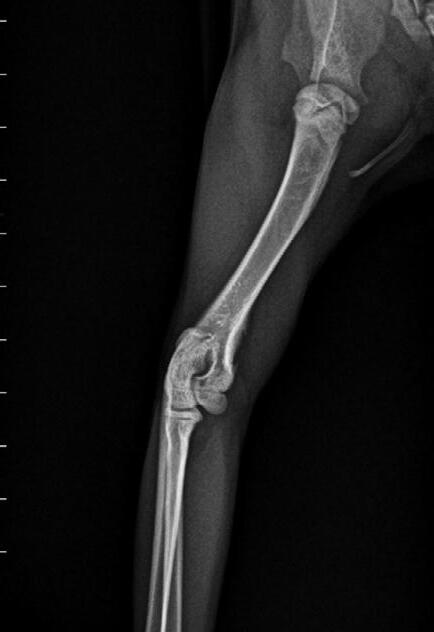

Tallulah presented as an 18-week-old Domestic Short Hair kitten with a persisting left forelimb lameness. On examination, she was uncomfortable on manipulation of the forelimb and painful on palpation over the left humerus. She was quiet and played for shorter time periods. She was in good body condition and eating well but had a temperature of 39.4° C. Radiographs suggested osteomyelitis of the left humerus, with extensive moth-eaten osteolysis of the diaphysis ( Figure 4).

She was given Amoxyclav (25mg/kg BID) and re-examined and radiographed 2 weeks later—by this time she was absolutely normal, with no pain or lameness and a normal temperature.

She is currently still on her antibiotics for 8 weeks before she is reviewed for repeat X-rays and spey!

Figure 5. Lateral radiograph of the affected left leg (A) compared with the normal contralateral right leg (B) 2 weeks after stating amoxicillin clavulanate. Note the irregular areas of osteolysis of the left humerus are MUCH IMPROVED.

Figure 6. Lateral radiograph of the affected left leg (A) compared with the normal contralateral right leg (B) 8 weeks after stating amoxicillin clavulanate. Note the irregular areas of osteolysis of the left humerus are MUCH IMPROVED after extensive remodelling.